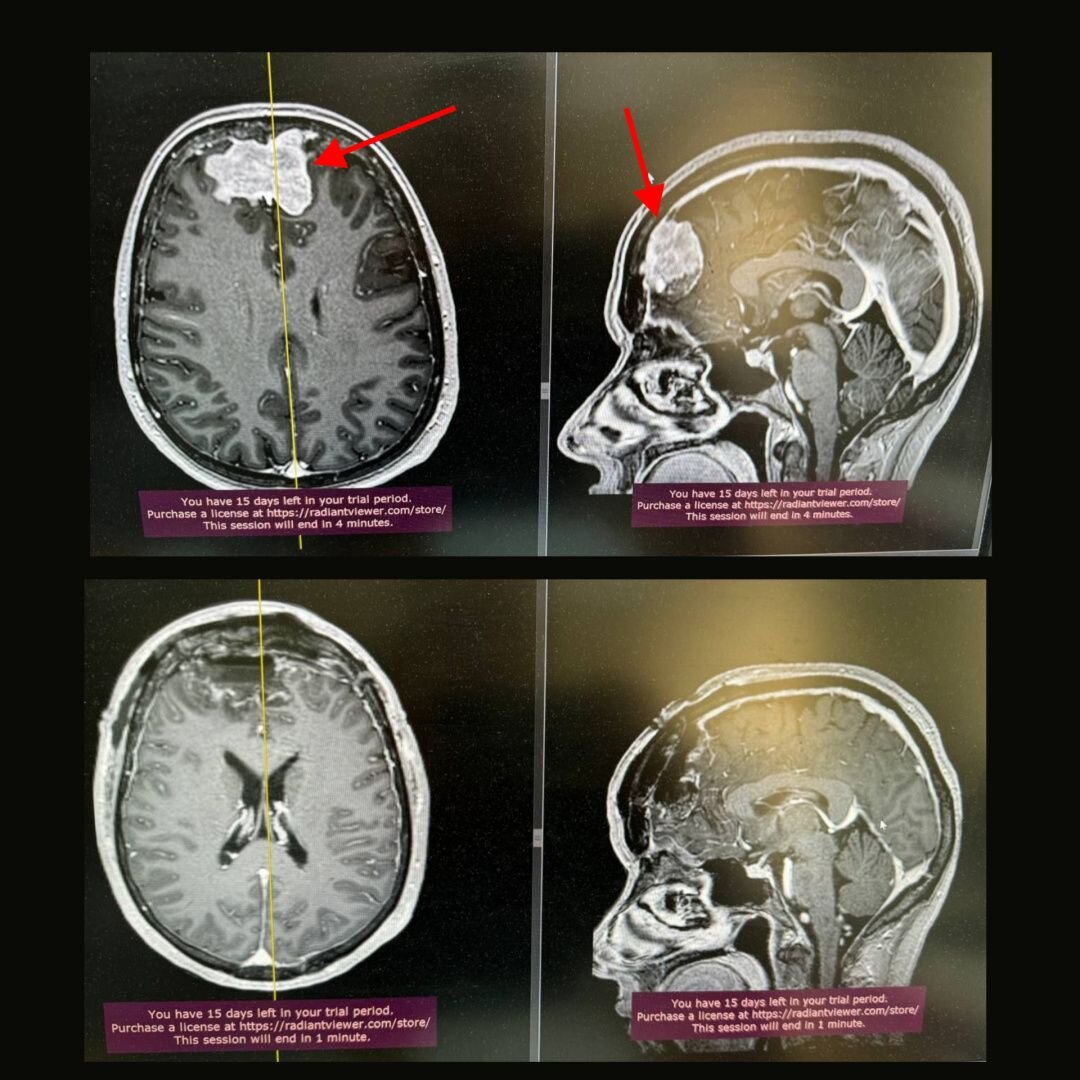

Менингиома, клинический случай

_ Данный клинический случай показателен! Не терпите головную боль, запишитесь на прием к доктору! Пациентка с жалобами на частые головные боли обратилась в Институт Мозга. На МРТ обнаружена менингиома верхнего сагиттального синуса и Фалькса.

Это доброкачественная опухоль, которая медленно росла и постепенно отодвигала лобные доли головного мозга. Кроме частых головных болей пациентку ничего не беспокоило. Выполнено тотальное удаление опухоли с перевязкой верхне-сагиттального синуса (это венозный коллектор, расположенный вдоль верхней части мозга).

Из особенностей: опухоль проросла в костную ткань и твердую мозговую оболочку. Была выполнена пластика твердой мозговой оболочки из фасции бедра.